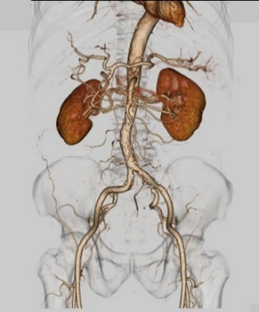

CTで撮像された薄い画像を重ね合わせ、ボリュームデータとして扱うことで任意の断面を構築することができます。立体的に表示することも可能で、例えば骨のみ表示させ回転しながら観察することで、手術支援や患者の皆様への説明に用いられます。

造影剤を用いた検査では血管や腫瘍の情報が得られ、腫瘍への栄養血管の走行を見たり骨と重ねて位置関係を把握することもできます。動脈瘤や閉塞部位についても多方向から観察ができるため手術前のシミュレーションにも用いられます。

腹部3D画像